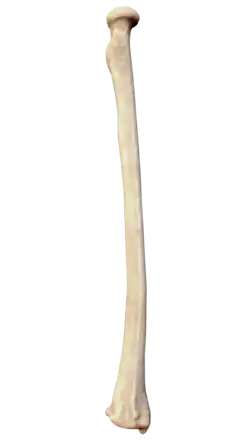

The radius or radial bone (pl.: radii or radiuses) is one of the two large bones of the forearm, the other being the ulna. It extends from the lateral side of the elbow to the thumb side of the wrist and runs parallel to the ulna. The ulna is longer than the radius, but the radius is thicker. The radius is a long bone, prism-shaped and slightly curved longitudinally.

The radius has a body and two extremities. The upper extremity of the radius consists of a somewhat cylindrical head articulating with the ulna and the humerus, a neck, and a radial tuberosity.[1] The body of the radius is self-explanatory, and the lower extremity of the radius is roughly quadrilateral in shape, with articular surfaces for the ulna, scaphoid and lunate bones. The distal end of the radius forms two palpable points, radially the styloid process and Lister's tubercle on the ulnar side. Along with the proximal and distal radioulnar articulations, an interosseous membrane originates medially along the length of the body of the radius to attach the radius to the ulna.[2]

The body of the radius (or shaft of radius) is prismoid in form, narrower above than below, and slightly curved, so as to be convex lateralward. It presents three borders and three surfaces.

The upper extremity of the radius (or proximal extremity) presents a head, neck, and tuberosity.